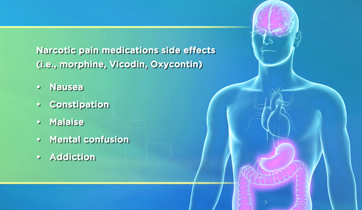

Pulsed Radio-Frequency Therapy

AMP Orthopedics,

Whitespace Healthcare Marketing

PRF Therapy is designed to accommodate the patient, the physcician, and the biotech marketer. It illustrates the MOA of a PRF device in treating inflammation. It also is compared to NSAIDs and other narcotics used for similar conditions.